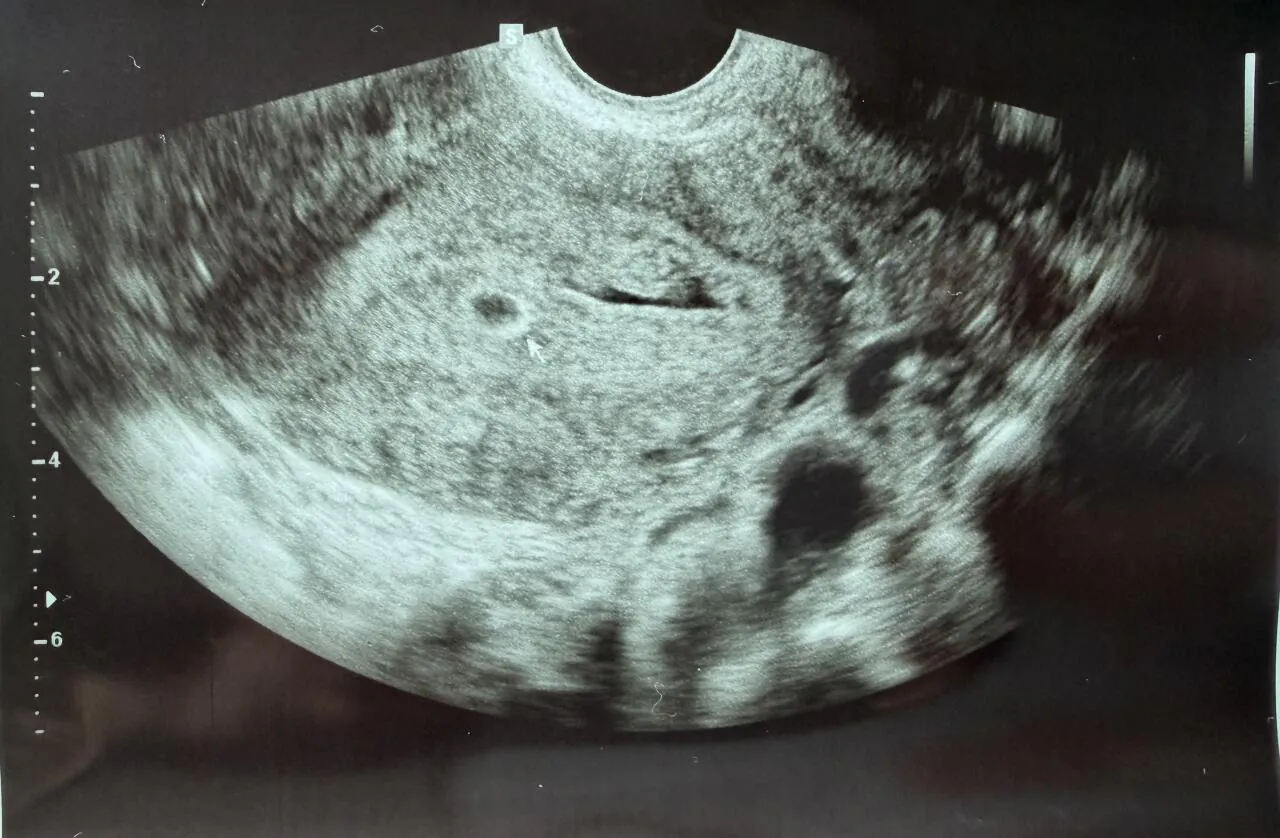

지난해 연말에 결혼을 했고 올해부터 차근차근 준비해보려고 했었는데 갑자기 아이가 생겼어요

현재 4주차인데 초음파에서 아기집만 보일 정도예요

건강하게 잘 자라주길 간절히 바라고 있습니다